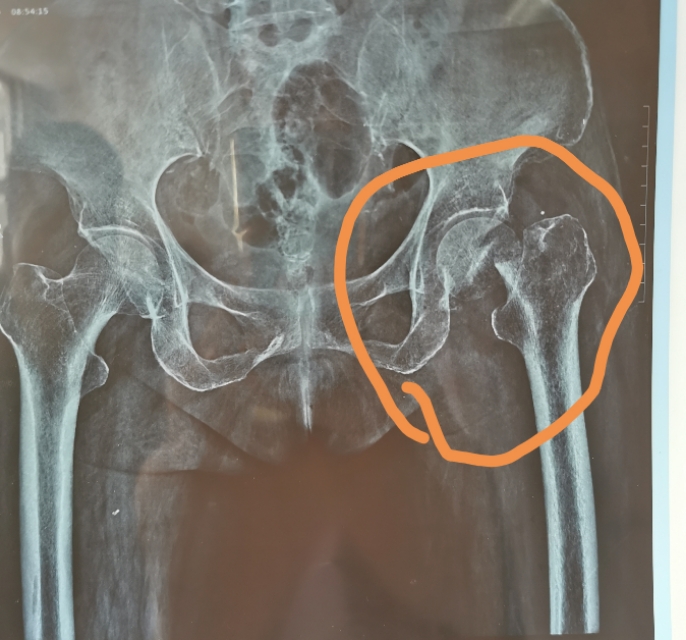

这是一位68岁的女性患者,在两个多月以前摔倒,发生了股骨颈骨折。当时据家属说骨折的移位并不明显,经过商量以后选择了在家卧床保守治疗。两个多月过去了,本以为已经差不多该愈合了,结果拍片子一看,股骨头完全移位,骨折长好无望了。

但是这里面有一个可能的风险,大家要知道,就是文章开头,我放的那张X光片,这个病人的家属说,他一开始移位也不明显,是在家里两个多月躺的过程之中,又发生了骨折的移位,这种情况是医生难以避免的。在家里有时候躺着翻身,坐起吃饭等等就有可能导致骨折移位。在你选择保守治疗的那一刻,你就要理解、接受并承担可能出现的再移位,再骨折的风险。